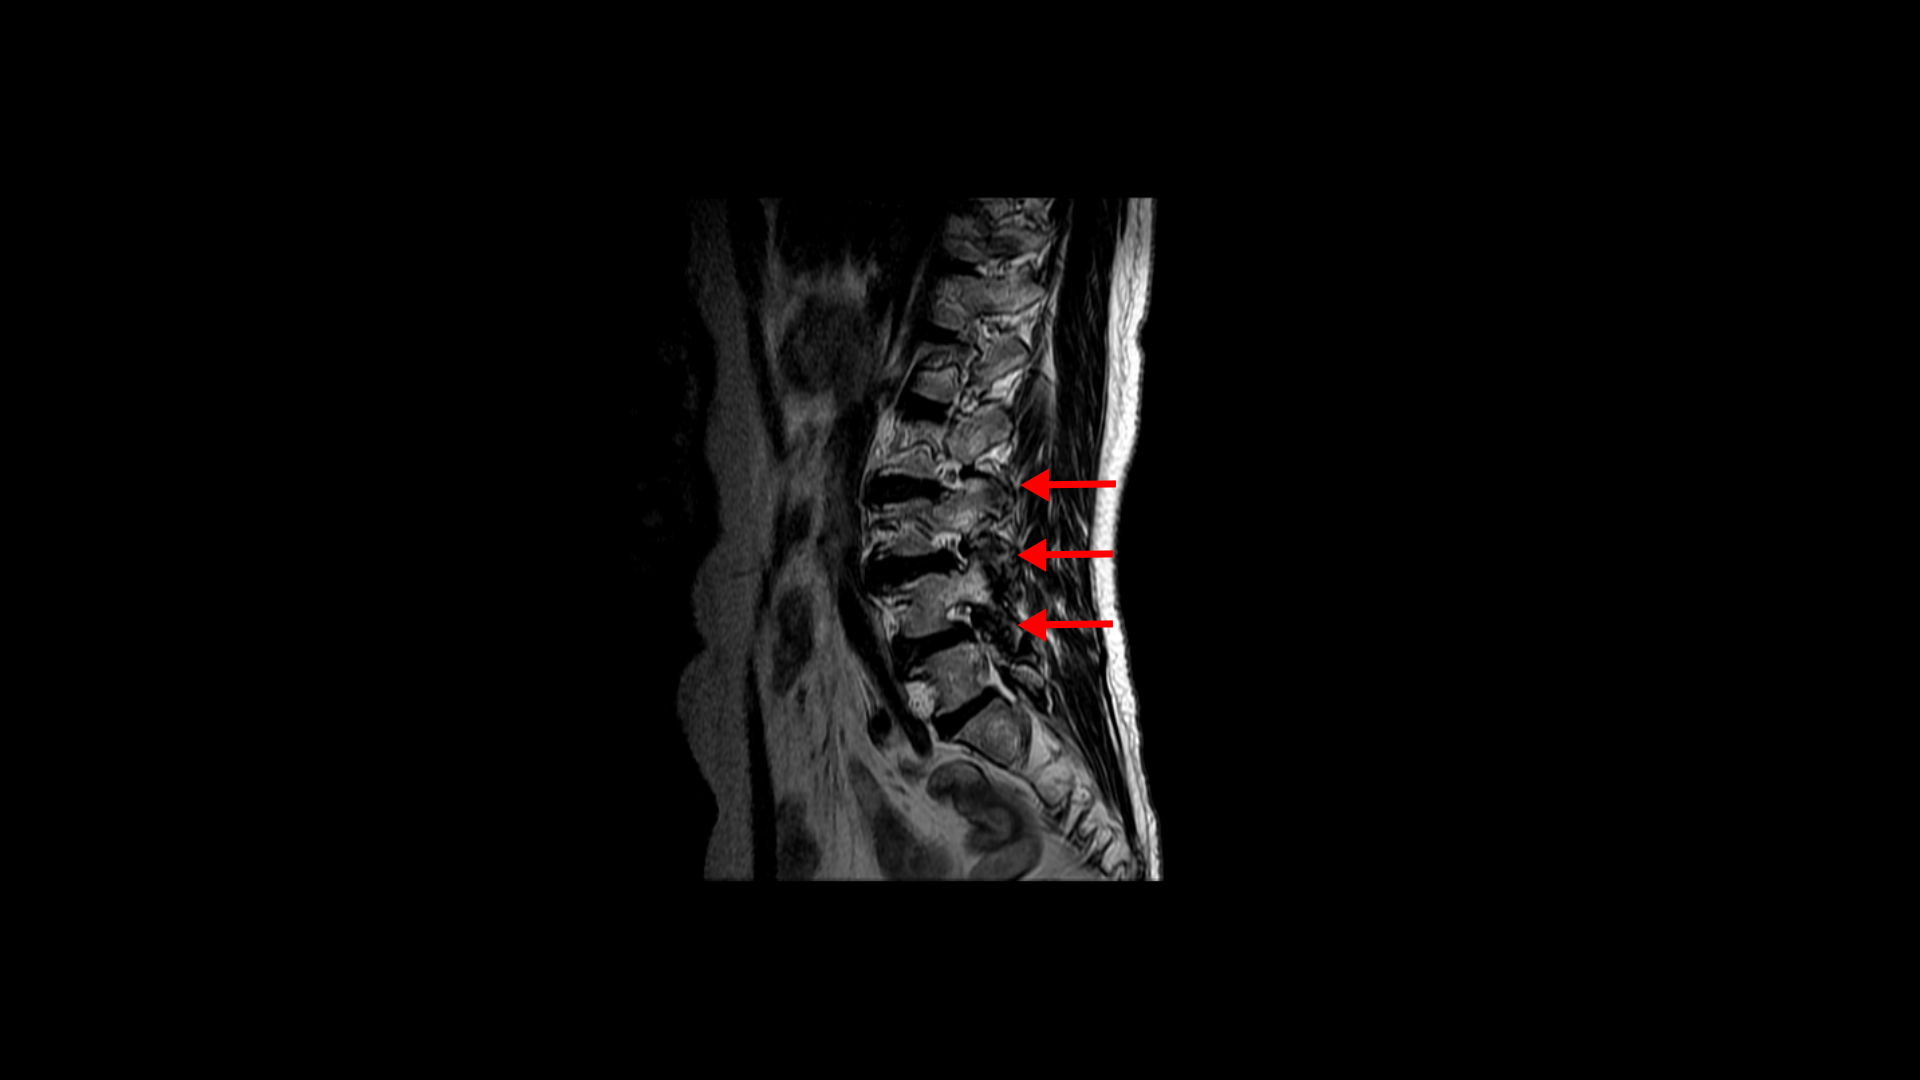

우선 이 환자분의 MRI를 함께 보겠습니다. 이 환자분의 척추에는 3번 4번과 4번 5번에 각각 1단계의 전방전위증이 있습니다.

3번 4번에는 왼쪽으로 디스크 탈출이 있고

중심성 협착도 있습니다.

그리고 4번 5번에도 왼쪽으로 퇴행성디스크와 후관절의 퇴행으로 신경 가지가 나가는 구멍이 좁아져 있습니다.

그리고 중심성 협착도 있습니다.

그런데 이 환자분의 제일 불편한 증상은 왼쪽이 아니고 오른쪽 엉치와 다리 증상입니다. 이분 오른쪽 신경 구멍들을 보면 전부 다 넓게 잘 열려 있습니다.

엉치와 다리 방사통을 일으킬만한 특별한 신경 눌림이 보이지 않는 것입니다. 그럼에도 불구하고 여러 마디의 전방전위증과 척추관 협착 그리고 디스크 탈출이 있으니까 그것을 원인으로 보고 신경 주사도 맞고 시술도 받으셨습니다. 그러나 별 효과는 없었습니다. 그리고 대학병원에서도 결국은 수술밖에 방법이 없다고 수술을 권유하였습니다.